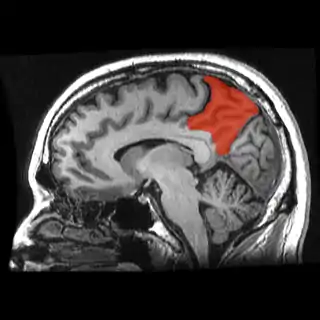

![]() Corte de una IRM sagital mostrando el precúneo en rojo. | ||

Se denomina precuña o precúneo a una parte del lóbulo parietal superior oculto en la fisura longitudinal medial entre los dos hemisferios cerebrales. A veces se describe como la zona media de la corteza parietal superior. El precúneo está limitado anteriormente por la rama marginal del surco cingulado, posteriormente por el surco parietooccipital, e inferiormente por el surco subparietal. Está involucrado con la memoria episódica, procesamiento visuoespacial, reflexiones sobre uno mismo, y aspectos de la conciencia.

El precúneo es una pequeña circunvolución en forma de cuña en la superficie medial del lóbulo parietal del cerebro, delimitada posteriormente por el surco parietooccipital y anteriormente por el lóbulo paracentral.